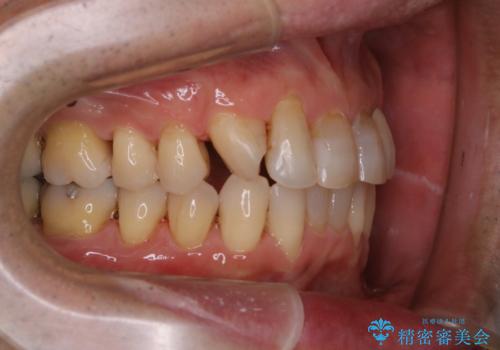

- インビザラインでの矯正中も、コーヒーを頻繁に飲むためステインが気になるとのことでした。PMTC60分コースでなんとかクリーニングを行いました。

インビザライン治療中には、歯の表面にアタッチメント(効率的に歯の移動をするもの)を設定します。そのため歯ブラシでは届きにくい細かい部分などに、歯石や着色がついてしまうことがあります。着色などを放置していると、着色なのか、虫歯なのかの判別もしずらく正確にお口の中の状態を診断できません。